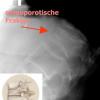

Die Kyphoplastie und die Vertebroplastie sind Techniken zur Behandlung eines Wirbelkörperbruchs infolge Osteoporose oder Metastase. Beiden Techniken gemeinsam ist die Einspritzung von Knochenzement in den betroffenen Wirbelkörper, was häufig sofort zu einer Linderung der Schmerzen führt. Bei der Kyphoplastie wird jedoch zusätzlich eine Aufrichtung des zusammengebrochenen Wirbelkörpers über einen in den Wirbelkörper platzierten Ballon, der mit Flüssigkeit (Kontrastmittel) unter hohem Druck (bis zu 250 PSI) befüllt wird, durchgeführt. Dadurch entsteht in dem Wirbelkörper ein Hohlraum, der dann mit einer speziellen Technik mit Knochenzement befüllt wird.

Diese Methode ist im Vergleich zu vielen anderen Techniken der Wirbelkörperzementierung sehr sicher und nebenwirkungsarm, da der Zement nicht flüssig sondern zäh ist und mit nur wenig Druck eingebracht wird. Zudem wird durch die Aufrichtung die gefürchtete Buckelbildung verhindert.